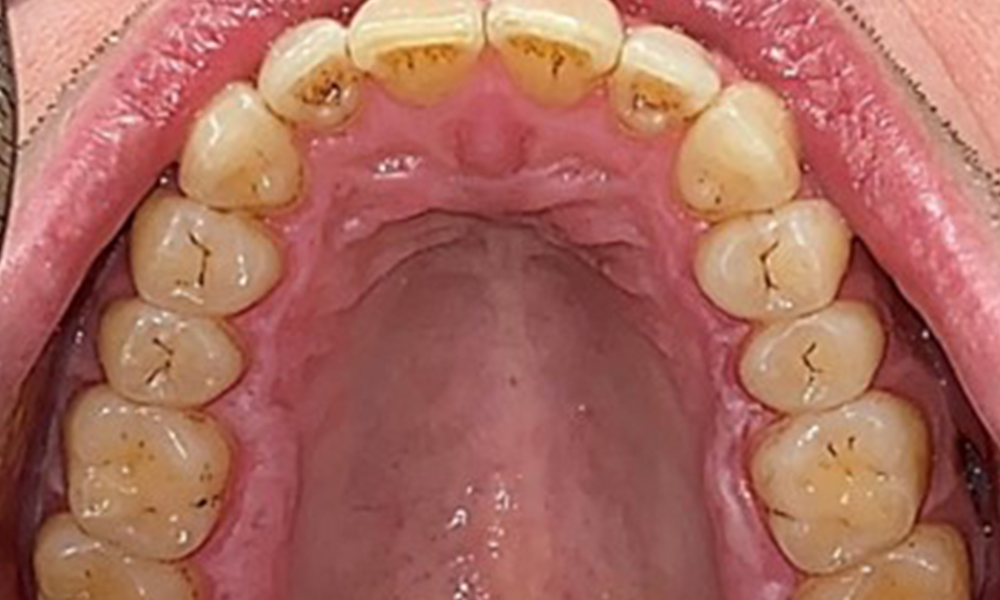

Occlusal view of the maxilla, © Dr R. Krapf

Fig. 3: Occlusal view of the maxilla, © Dr R. Krapf

Extraoral and intraoral findings

There were no pathological extraoral findings. During intraoral examination, inspection of the frontal view revealed brownish discolouration near the keratinised gingiva and at the transition to the moveable mucosa (Fig. 2), which could be attributed to nicotine consumption. Whitish mucosal lesions were observed on the palate, particularly near the maxillary molar palatal surfaces, indicating increased keratinisation and can also be attributed to nicotine consumption. The tongue was covered with a removable white and brownish coating.

The patient has full dentition with a total of 28 teeth. There were noteworthy erosions and attritions. (Fig. 4, Fig. 5). Due to bruxism, the patient has been wearing a splint with an adjusted bite block at night for many years. The erosions were caused by long-term consumption of isotonic beverages. No periodontal bone loss or active caries were observed.

Full complement of adult teeth with no caries or radiologically recognizable bone loss was observed (Fig. 6). Radiological enamel and cusp loss were particularly evident on 36 and 37.